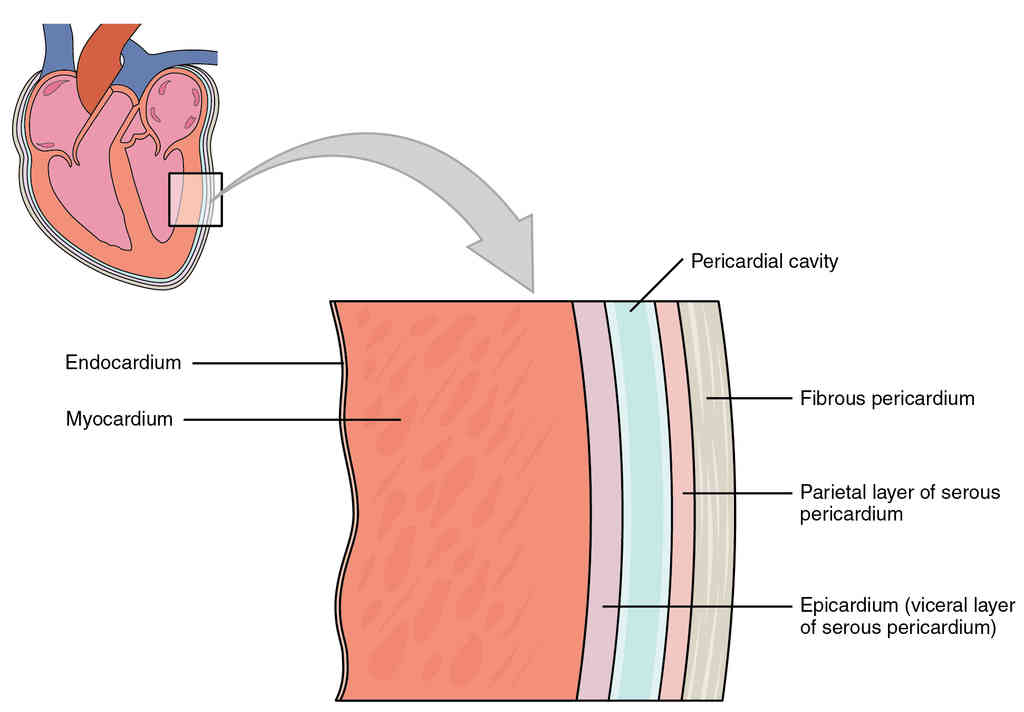

This page is under construction. For now, it is just a resource of the images found in the OpenStax Anatomy and Physiology Handbook. It wil slowly change into a revision tool. Each slide has a number. Use this to refer to the slide. When completed, it will have an unlabelled section, with labelled slides in parallel. On the unlabelled slides, write your answer and use the labelled slide to assess yourself. Keep track by also noting the number on each slide. Improvement at each attempt is important, more so than full marks on a first attempt.